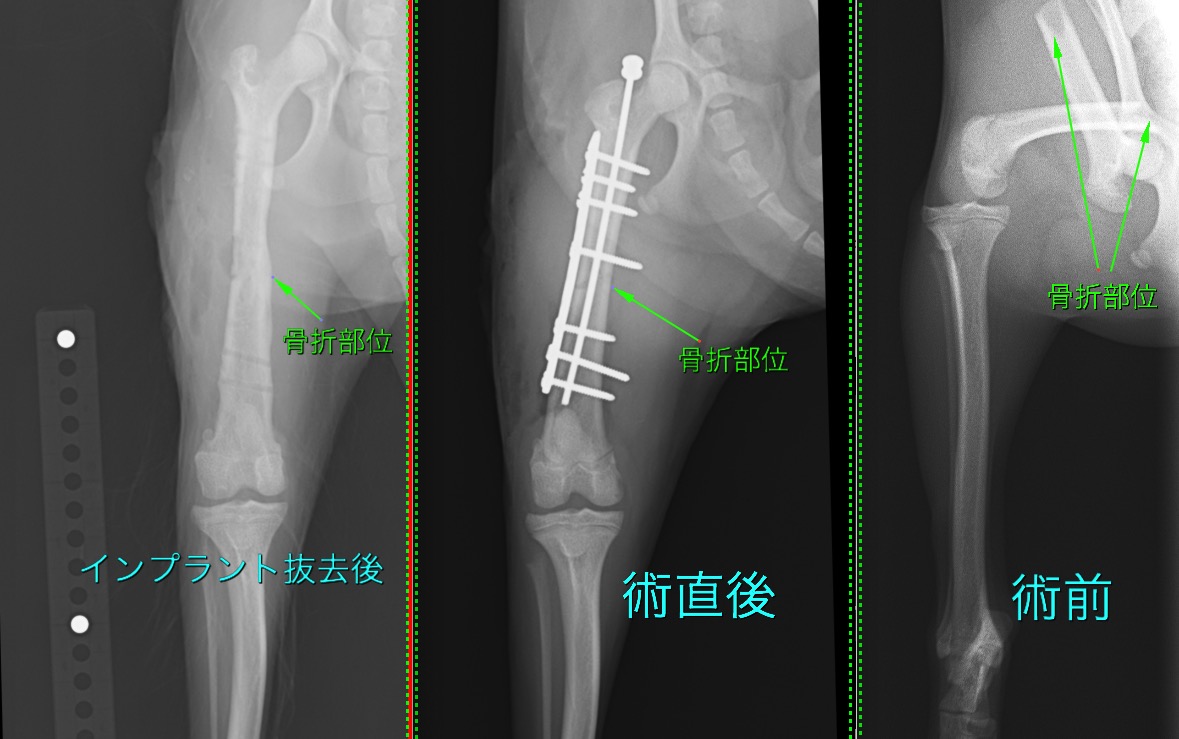

大腿骨骨幹部骨折の小型犬の1例(整形外科、骨折手術、後ろ足、プレート、ピン)

強い衝撃により大腿骨(後ろ足のももの骨)を骨折してしまったわんちゃんです。

髄内ピンとプレートによる”プレートロッド法”により整復しました。

術後1か月後から段階的にインプラントを間引き、術後2か月半ですべてのインプラントを抜去しました。

術後の経過は良好で、走ったり、ジャンプしたり、問題なく生活できているそうです。